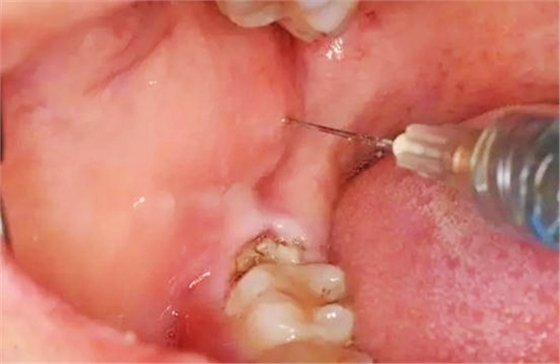

圖5.局部無痛阻滯麻醉